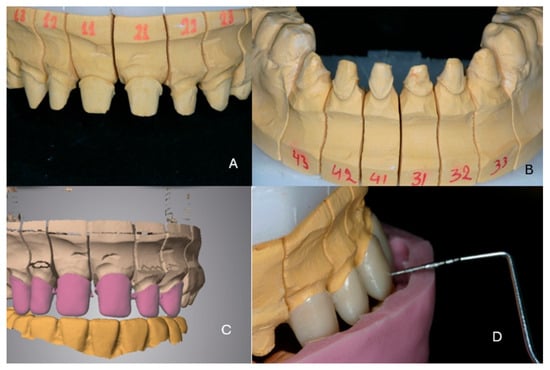

2. Case Presentation